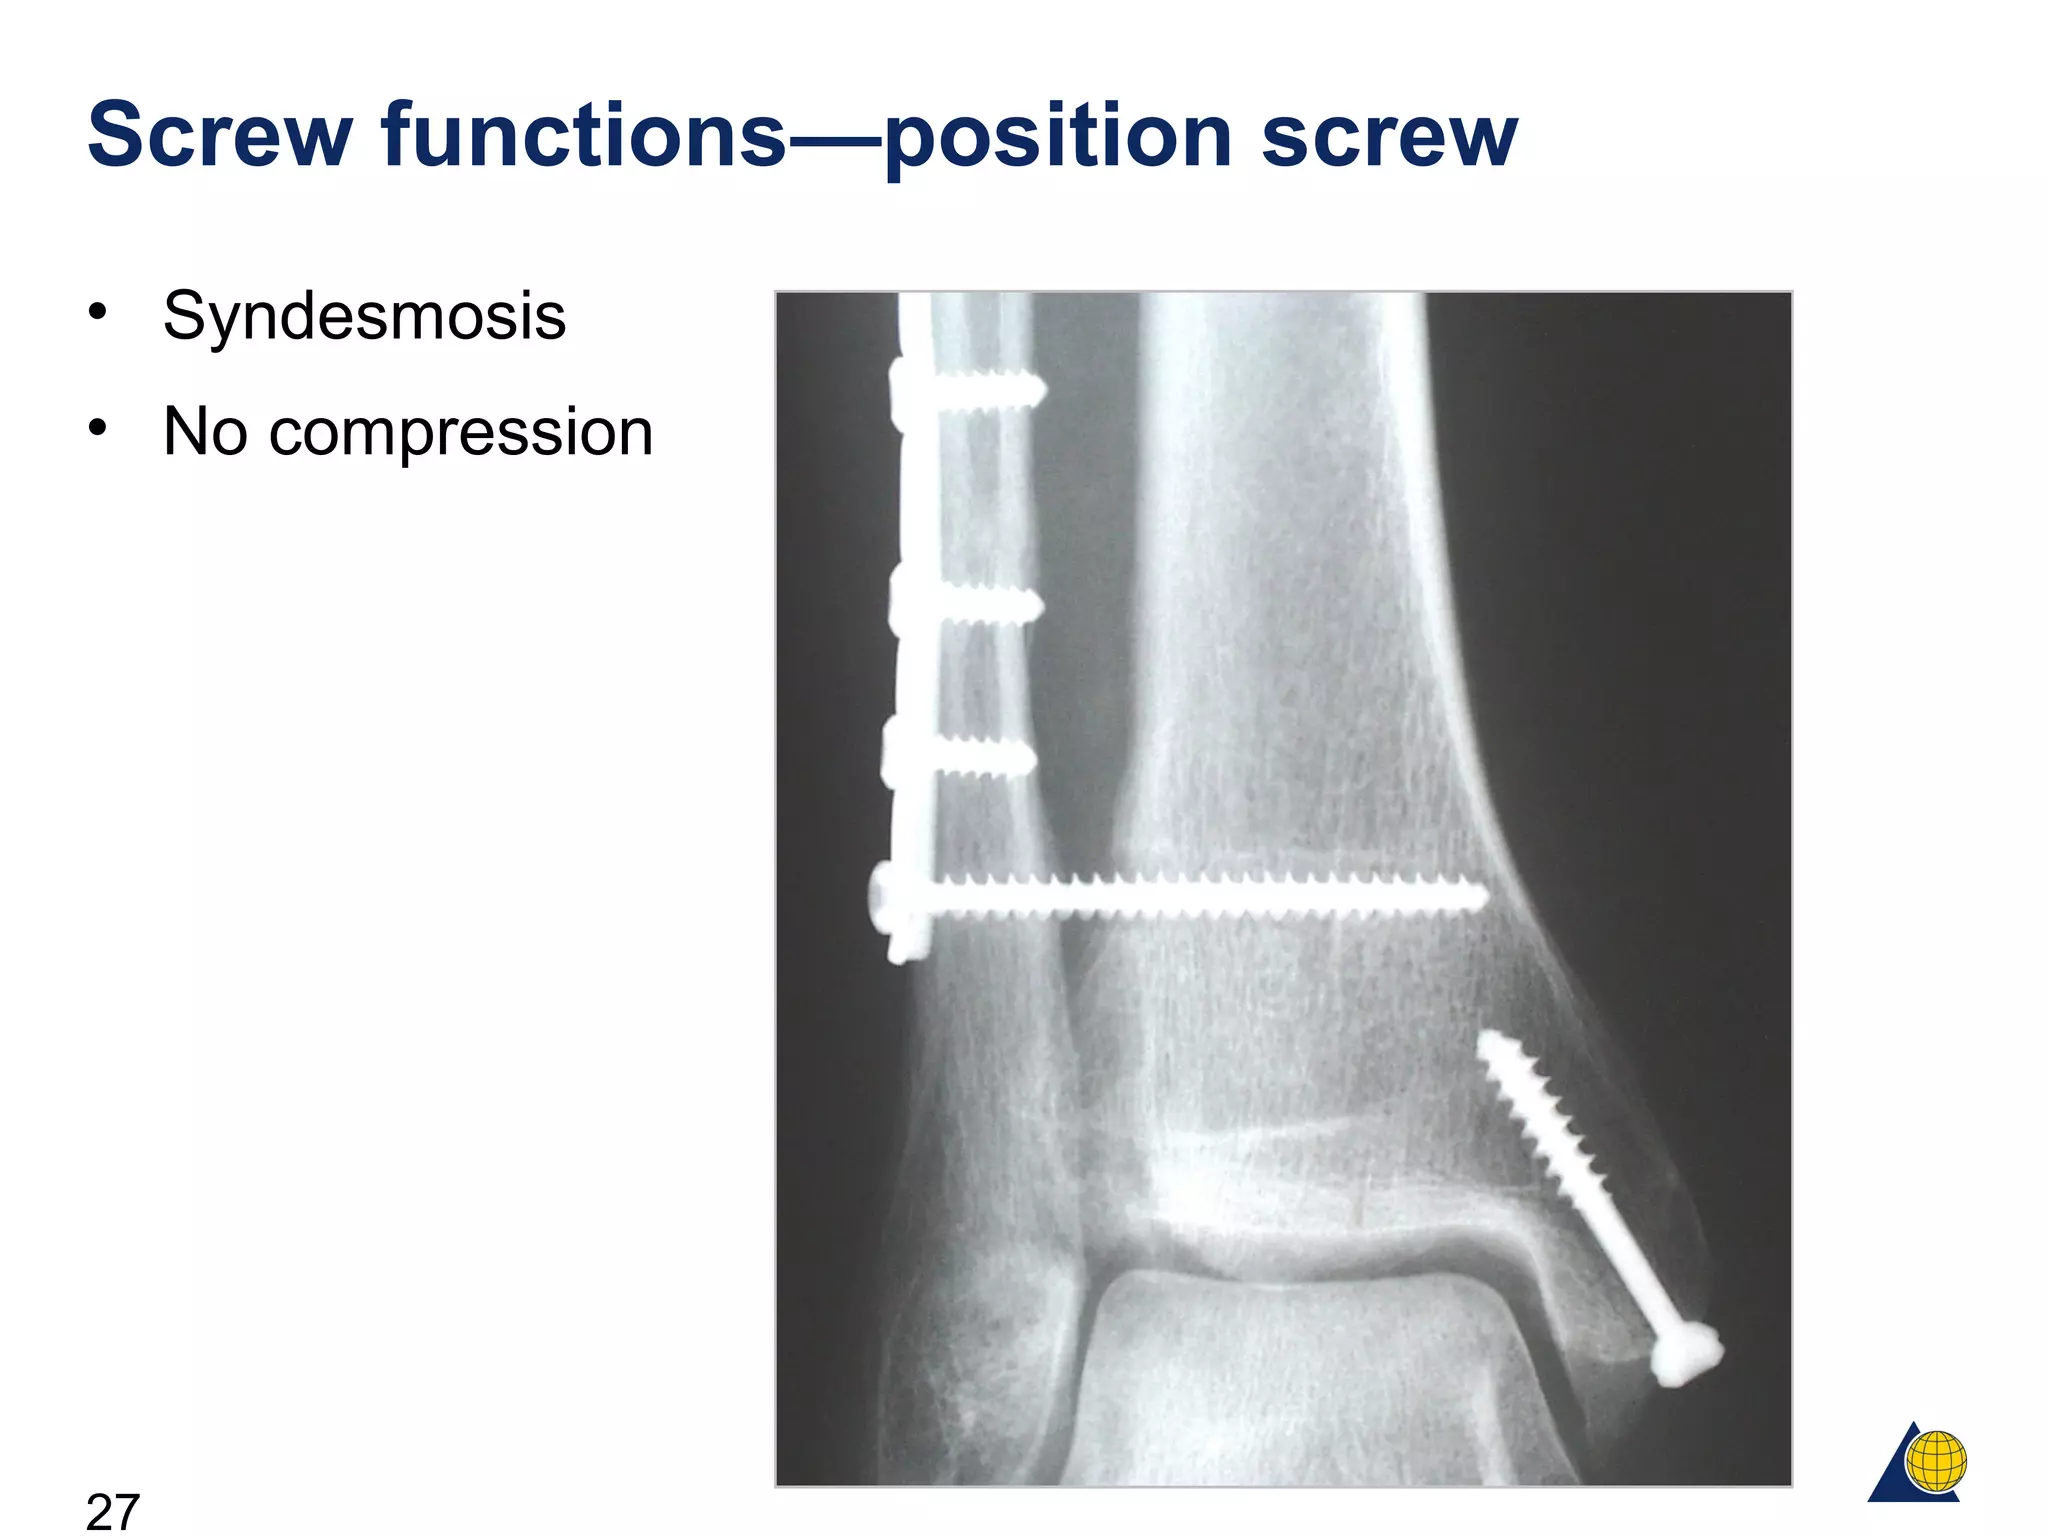

Screw functions—position screw

• Syndesmosis

• No compression